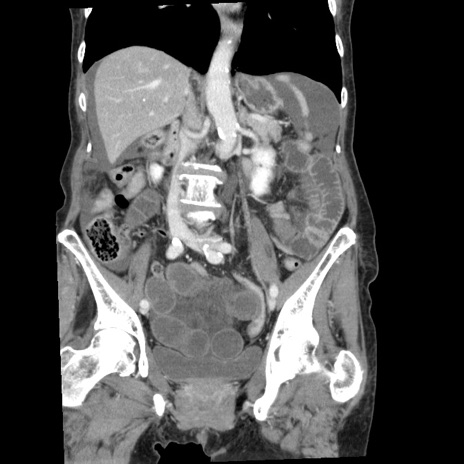

症例1(冠状断像)

【症例】80歳代女性

【主訴】腹痛

【現病歴】8時間前から腹痛あり来院。

【既往歴】糖尿病、脂質異常症、子宮体癌にて子宮全摘術

【身体所見】意識清明・会話良好だが腹痛で苦悶様、全腹部にわたって反跳痛と圧痛あり

【データ】WBC 13600、CRP 0.14、LDH 224、CK 90